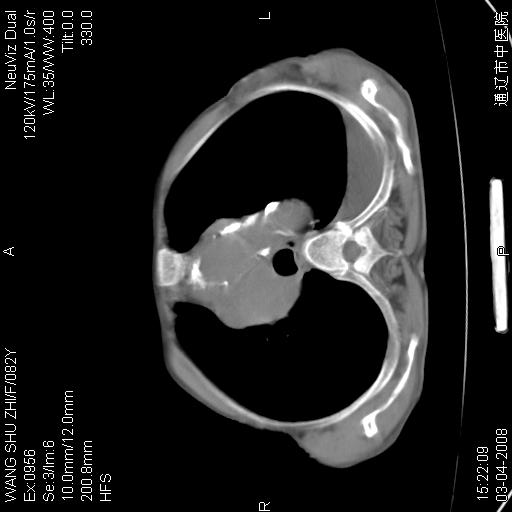

该患者为女性,82岁,既往肺心病、心衰病史。上纵隔影增宽,是否为畸形扩张的血管呢?因该患者年龄太大,又有较严重心脏病,故不适宜做增强检查。

中纵隔肿块最多见是淋巴瘤,而且以hd为多见,呈侵袭性生长,纵隔脂肪间隙消失,再加上心包和双侧胸腔积液,考虑为淋巴瘤(hd)应该说比较准确的。至于说是畸形的血管可能性小,因为畸形血管周围脂肪间隙应该存在。

纵隔淋巴结转移或淋巴瘤;双侧胸腔积液,心包积液。肺窗呢?

病史太简单,年龄太大,首先考虑转移!左侧腋窝亦见肿大淋巴结。

左侧腋窝及纵隔内见多个肿大淋巴结影,左侧少量胸腔积液,心包积液,支持淋巴瘤可能性大,不除外淋巴结转移。